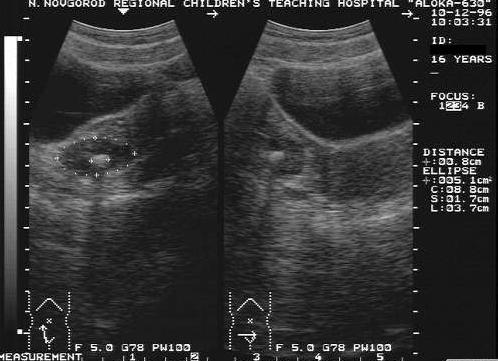

Внутривагинальное обследование

Диагностика

Только специалист сможет подтвердить наличие кальцинатов в яичниках или их отсутствие. Для определения размера и места расположения женщине стоит посетить УЗИ, которое выполняется несколькими способами:

- Трансабдоминальное УЗИ. Диагностика в этом случае проводится через живот. Для того чтобы аппарат УЗИ дал более точные данные, на живот женщины наносится специальный гель. Вся процедура не доставляет пациентке каких-либо неприятных или болевых ощущений.

- Трансвагинальное УЗИ. Через влагалище вводится специальный датчик, который показывает информацию о яичниках с близкого расстояния. Этот метод считается наиболее точной диагностикой заболевания.

- Трехмерное УЗИ. В последнее время является популярным методом и дает достоверные сведения о патологическом процессе, но имеет на порядок выше стоимость. При таком виде УЗИ врач получает трехмерное изображение исследуемого органа.

Кальцинаты обычно выявляют с помощью рентгеновских лучей или УЗИ. Датчик выявляет точечные гиперэхогенные очаги размером от 1-3 мм.